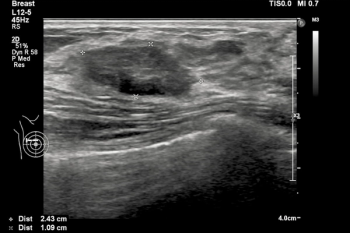

Emerging breast ultrasound research showed the use of computer-aided diagnosis (CAD), powered by deep learning, led to 24 percent and 36.9 percent improvements in accuracy and specificity, respectively, in the use of BI-RADS classifications by radiologists without breast ultrasound expertise.

Researchers found that a deep convolutional neural network, incorporating B-mode ultrasound and shear wave elastography data, had nearly an 88 percent sensitivity rate for predicting neoadjuvant chemotherapy response in patients with breast cancer.